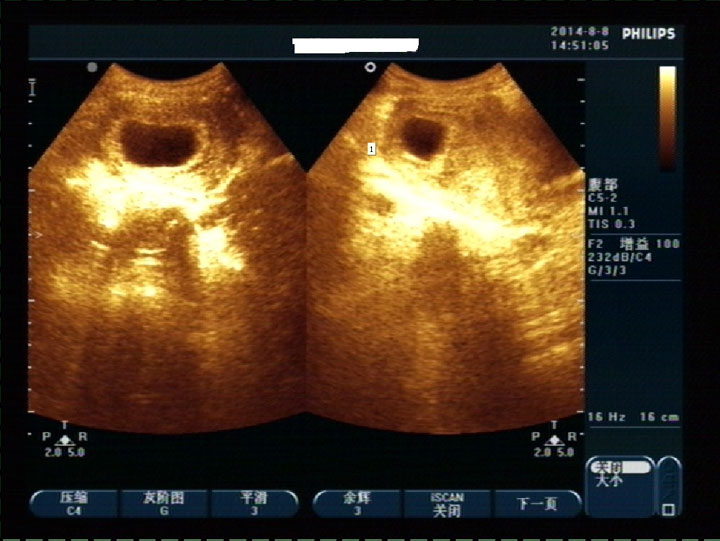

通过四维彩超知道胎宝宝的性别,是最简单最直观而且准确率高的方法,那么直接看胎儿生殖器官可以看性别,那民间传说的看孕囊看其他数据也可以看男女吗?一起来看看吧。

四维彩超孕囊数据看性别

孕妈妈间流传着这么一个传说,孕早期看孕囊形状可以看性别:像茄子或长条状的是男宝宝可能性大(椭圆形),圆圆的是女宝宝的可能性大(正圆形)。

如果对孕囊形状看的模糊没有把握,可以根据孕囊的数据来预估孕囊的形状。如果孕囊长和宽的相差在一倍以上(孕囊形状就会偏向椭圆形),男宝宝可能性大。孕囊的长和宽相等,女宝宝可能性大(孕囊形状偏向正圆形)。

其实这种民间传说是没有根据的,孕囊的形状大小是由孕期时间、营养、着床位置、子宫大小等多种因素决定的。每个孕妈妈的子宫形状和大小都不相同,而孕囊的形状也会随着子宫形状而不同。6周之前因为胎儿太小,大家做B超时都需要憋尿,憋尿多的话子宫被压得扁一些,孕囊的形状也看起来扁一些(这真相让你不忍直视对吗)。

既然孕囊是一个立体的类圆体,如果B超照的角度不同,看起来也会不一样,所以你从这个角度看是长的,可能从另一个角度看又是圆的呢,单凭一张模糊的四维彩超平面图,就判断孕囊是圆是扁不可靠。而医生可以通过多角度的动态四维彩超去看孕囊的形状,并且测量出数据。所以医生是可以看到孕囊是偏正圆还是偏椭圆的,但是难道测量这些数据就是为了给大家猜测男女吗?

真相是:孕早期需要从孕囊的形状和大小来判断胚胎的发育情况,一般来说,孕囊的正常形态是近似于椭圆、饱满的,而有先兆流产征兆的孕囊,一般是呈细长形状。当孕囊特别细长,准妈妈则要当心流产了。如果你到9周左右,孕囊大小还停留在5、6周的状态,医生也会进一步排除是否胎停育呢。

四维彩超图有区别